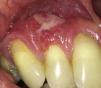

A middle-aged woman presented for evaluation of gingival swelling. She was previously diagnosed with hypoplasminogenemia and current plasminogen level was 29% (reference value: 78–130%). Intraoral examination revealed swelling of the right maxillary gingiva (Figure 1). Biopsy with routine histopathologic analysis revealed fibrinoid deposits and a mixed inflammatory infiltrate within the lamina propria, consistent with hypoplasminogenemia (Figure 2).